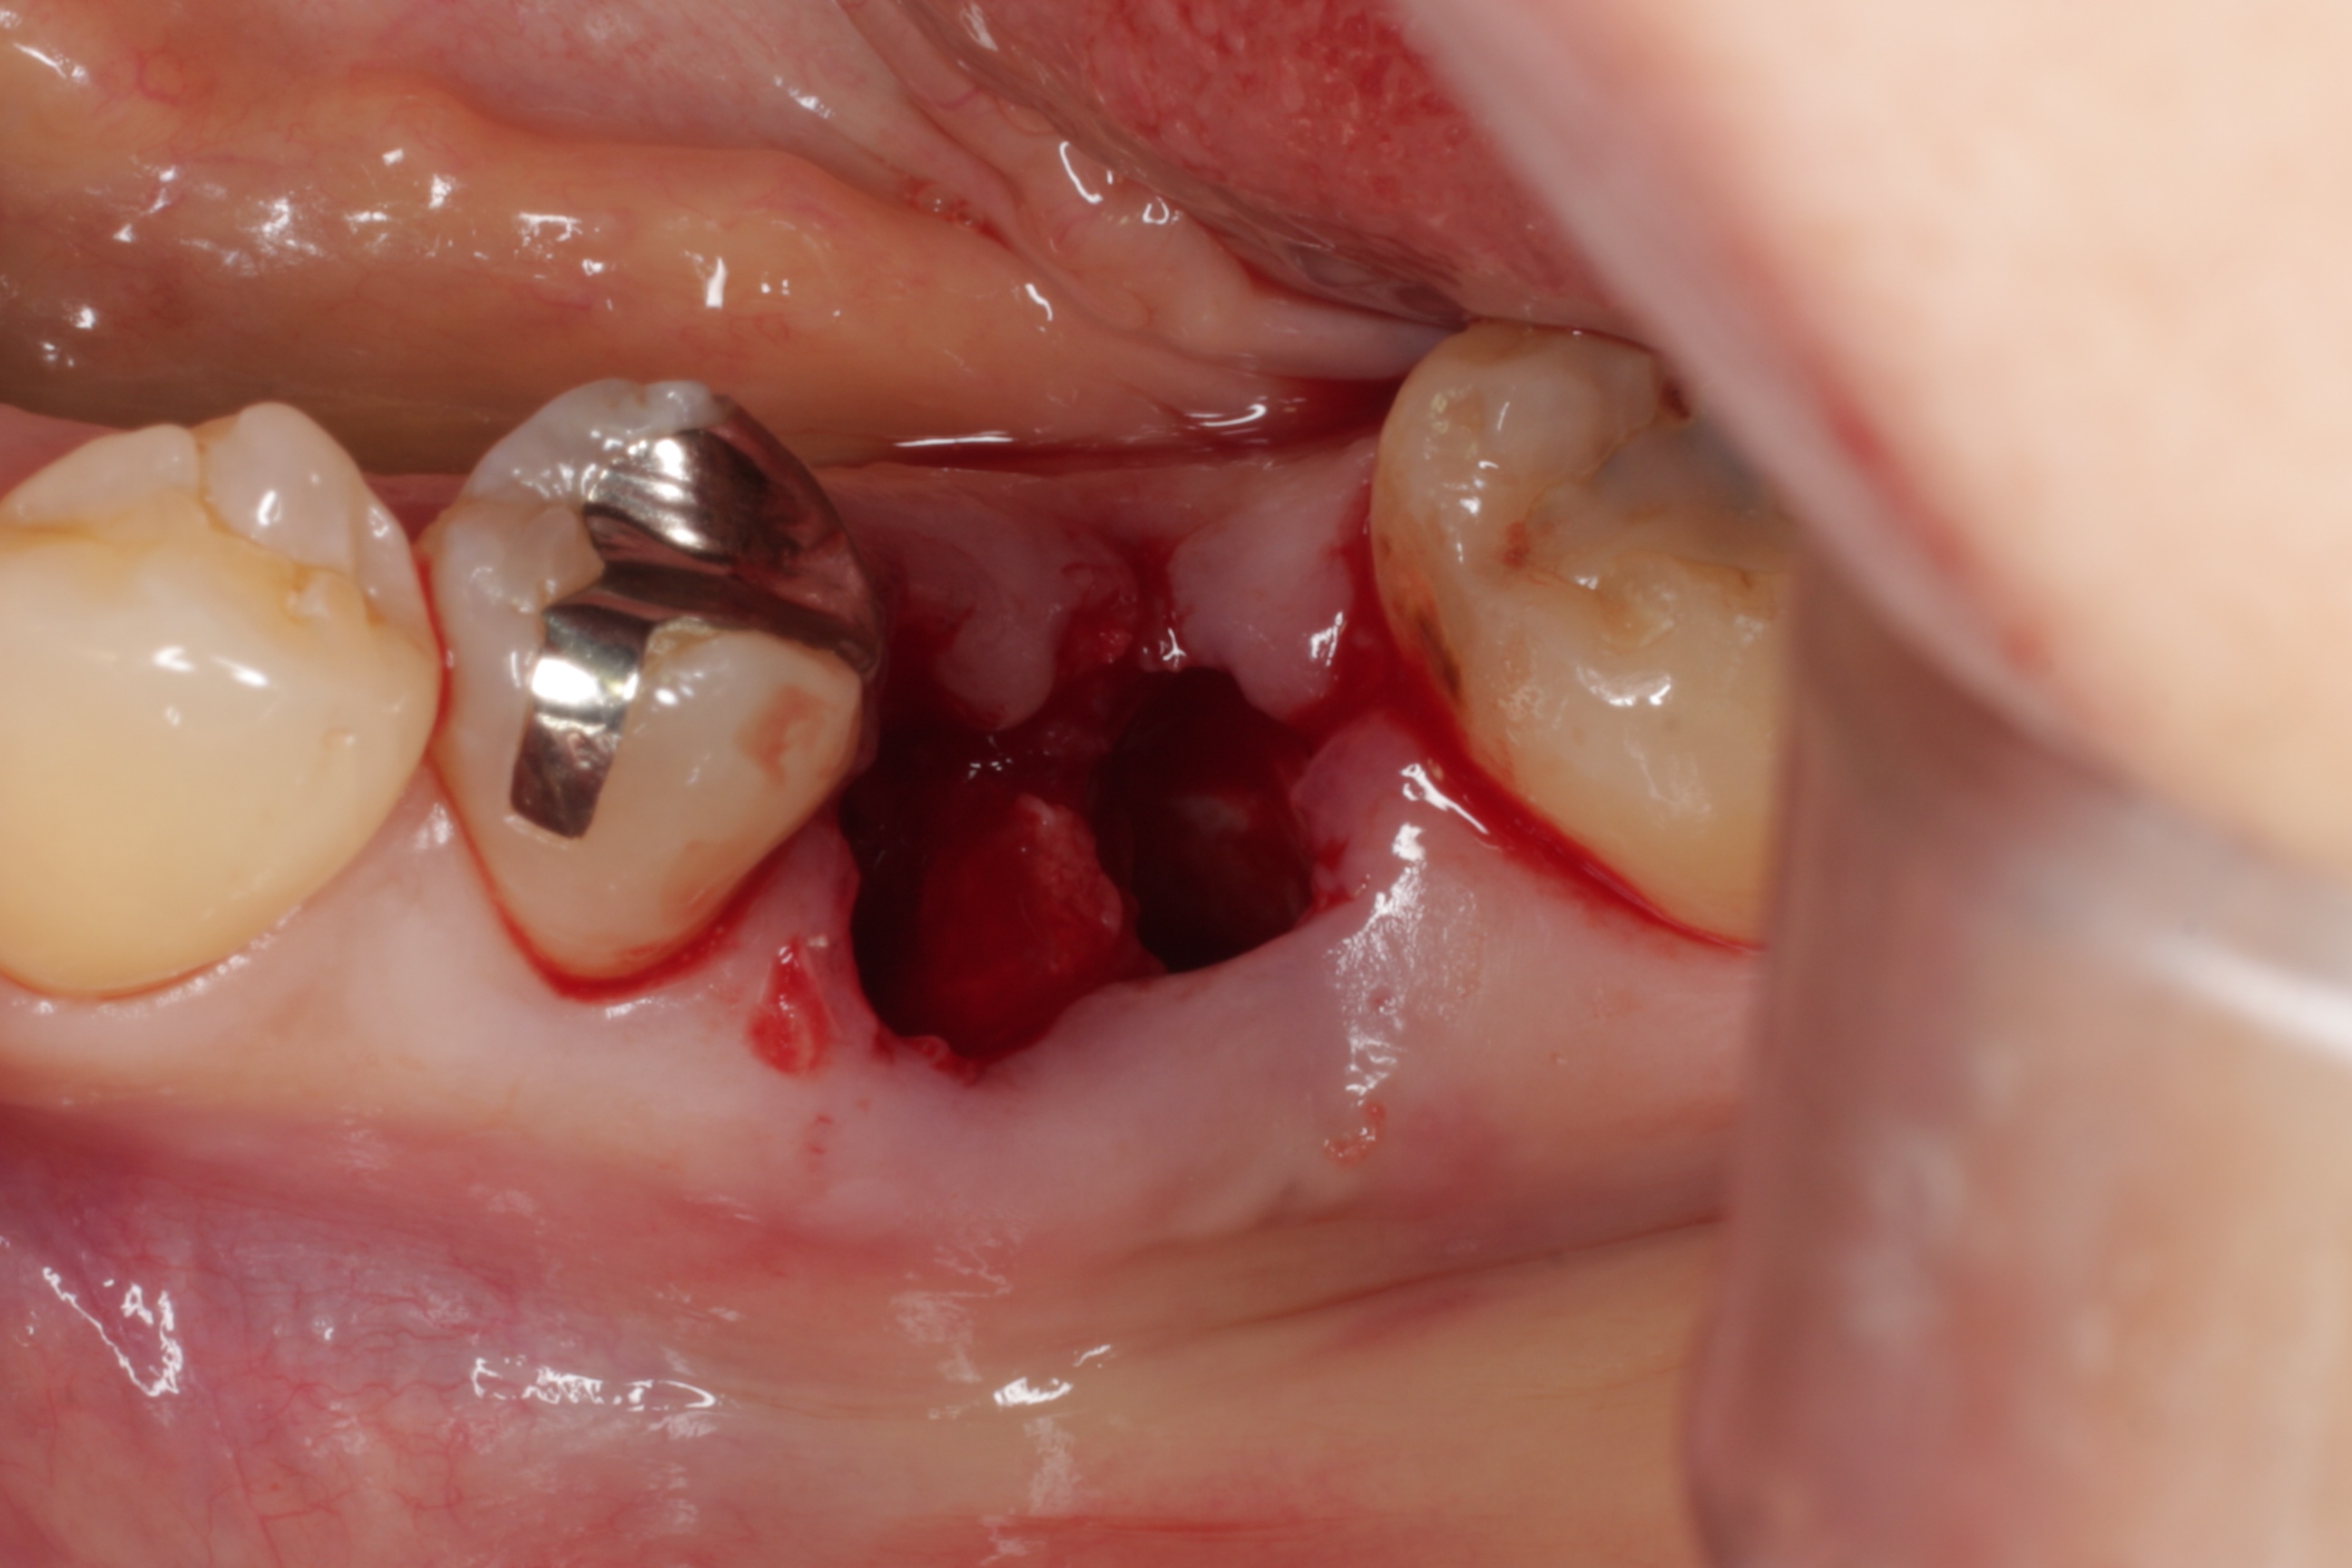

神経を取って、銀歯を被せていた6歳臼歯が割れてしまい、抜くしか方法がなかった患者さんの症例です。

3年前に割れてしまった歯を抜いて、すぐに親知らずを移植しました。